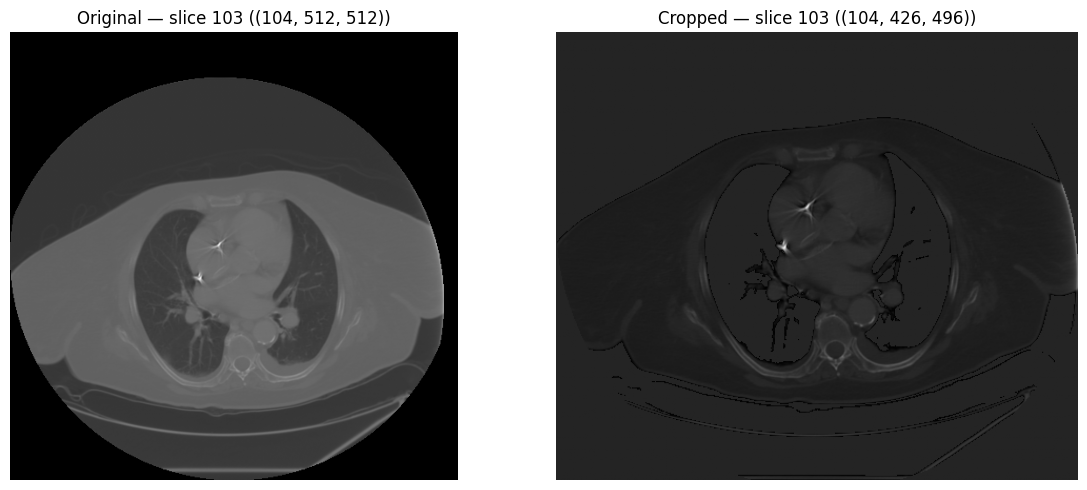

Spatial Operations

Standardize spatial resolution with isotropic resampling, and remove surrounding air with bounding-box cropping.

crop_to_roi.py

# Crop to body ROI (remove surrounding air)

body_mask = (image > -500).astype(np.uint8)

cropped = processor.crop_to_roi(image, body_mask)

print(f"Original shape:  {image.shape}")

print(f"Cropped shape:   {cropped.shape}")

Output

Original shape:  (104, 512, 512)

Cropped shape:   (97, 340, 370)

Original vs cropped volume